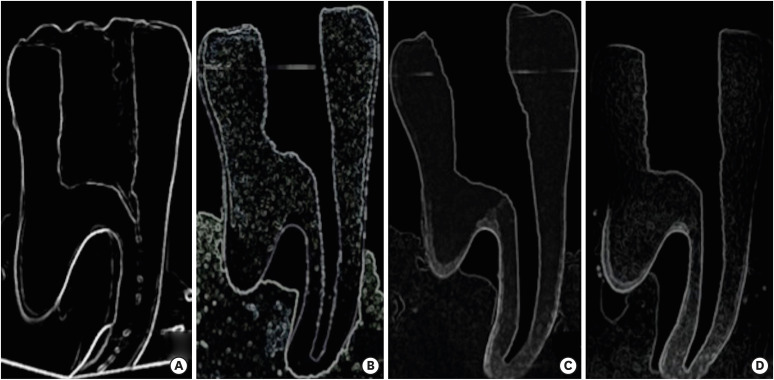

Research Article Micro-computed tomographic assessment of the shaping ability of the One Curve, One Shape, and ProTaper Next nickel-titanium rotary systems